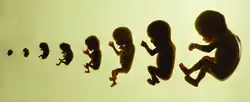

Chama-se de feto o estágio de desenvolvimento intrauterino que tem início nove semanas depois da fertilização (ou decima primeira semana de idade gestacional), quando já se podem ser observados braços, pernas, olhos, nariz e boca, e vai até o fim da gestação. O estágio anterior a este é conhecido como embrião. Após o parto, o feto passa então a ser considerado um recém-nascido.[1][2]

Em humanos, o estágio fetal começa nove semanas após a fertilização.[1] No início do estágio fetal, o feto normalmente tem cerca de 30 milímetros (1,2 in) de comprimento cabeça-nádega, e pesa cerca de 8 gramas.[1] A cabeça representa quase metade do tamanho do feto.[8] Movimentos semelhantes aos da respiração do feto são necessários para a estimulação do desenvolvimento pulmonar, e não para a obtenção de oxigênio.[9] O coração, mãos, pés, cérebro e outros órgãos estão presentes, mas estão apenas no início do desenvolvimento e têm operação mínima.[10][11]

Neste ponto do desenvolvimento, os movimentos e contrações descontroladas começam a aparecer à medida que os músculos, o cérebro e as vias começam a se desenvolver.[12]